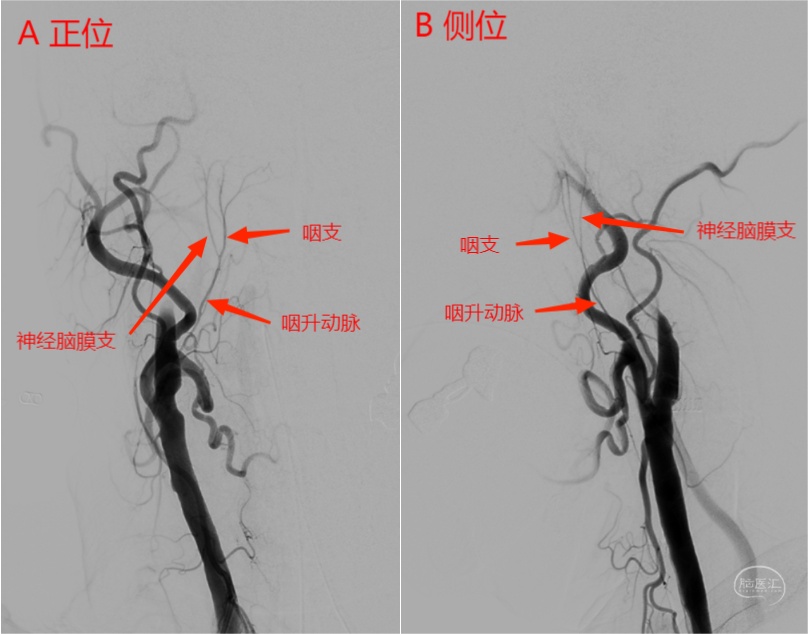

右侧颈内动脉闭塞患者,右侧咽升动脉自颈外动脉发出,左侧咽升动脉咽支自颈内动脉发出,神经脑膜支自枕动脉发出。

图12 右侧颈总动脉正位(A)及侧位(B)造影。由于颈内动脉闭塞,咽升动脉没有被颈内动脉遮挡而显示清晰,可见咽升动脉自颈外动脉发出,咽支走形在神经脑膜支的内前方。

图13 左侧颈总动脉正位(C)及侧位(D)造影。由于颈内动脉遮挡,咽升动脉在侧位显示不清。正位可见咽升动脉咽支自颈内动脉发出,神经脑膜支在枕动脉发出(详见下图3D及Xper CT)。

图14 左侧颈总动脉3D(E)及Xper CT重建(F)图像。可见咽升动脉咽支自颈内动脉发出,供血至咽部。

图15 左侧颈总动脉3D(G)及Xper CT(H)图像。可见咽升动脉神经脑膜支自枕动脉发出,向上走形进入舌下神经管。